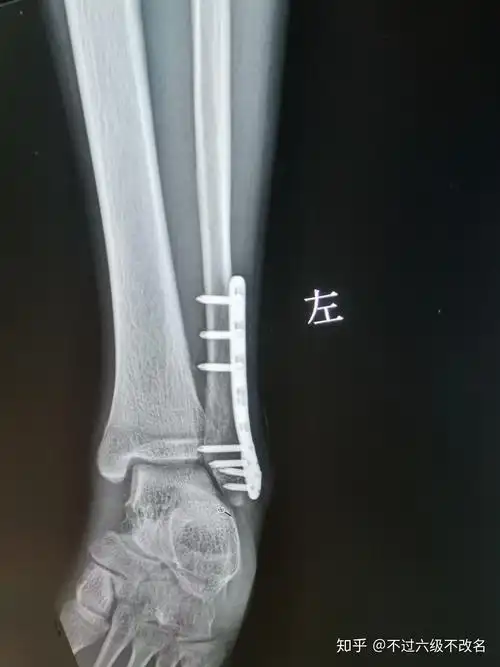

腓骨骨折 - 知乎